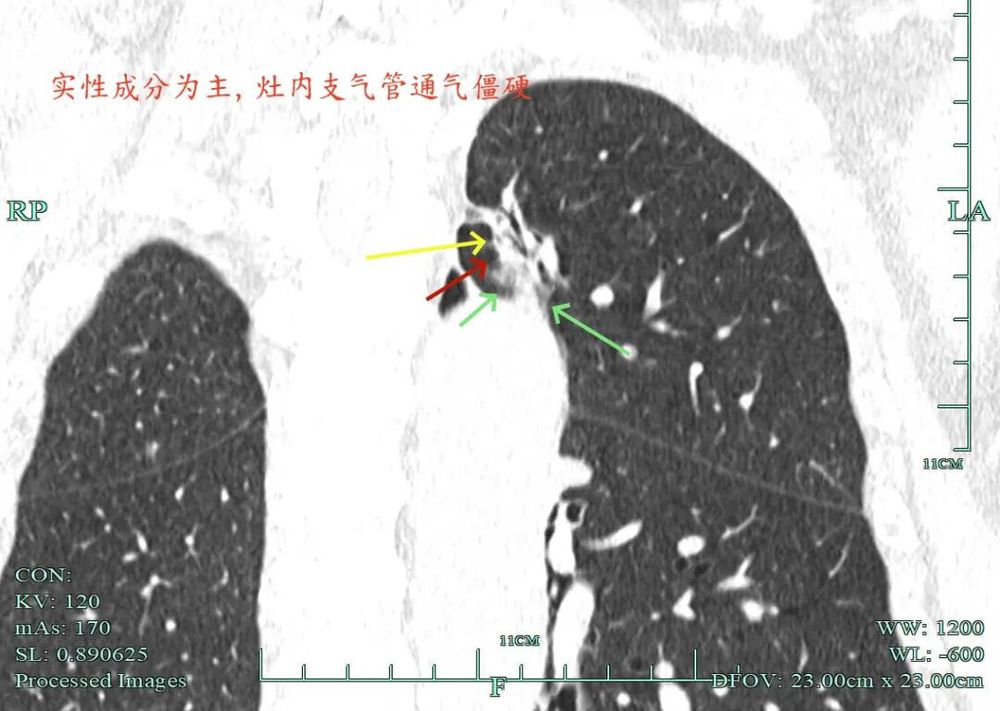

杭州市肿瘤医院影像展示与分析:

右上也有混合密度结节,实性部分缺乏膨胀性与收缩力,磨玻璃成分较淡,也偏糊,但持续存在仍得考虑肿瘤范畴可能性大。

此视角是混合密度,实性为主,贴胸膜近。

今天这位结友的病理类型稍差于术前的预测,但从其三年多随访情况来看,进展不算大厉害,第10组与第12组淋巴结均阴性的话,还是真早期的可能性还是较大的。后续倾向暂随访观察,可以采取相对稍积极的随访策略,比如两年内4个月复查一次,三到五年内半年复查一次,五年后再年度复查;而且右侧的病灶要在随访进展或身体恢复良好后微创局部楔形切除。期间万一有转移,其实是伪早期的话,则基因检测并全身性治疗。其实今天这种病灶在临床中被判断为炎性的并不少见,尤其是非胸外科医生。因为胸外科的一般相对积极,警惕性高些。在我的公众号上其实也分享过多例这种看着似乎是炎性,但长时间随访不好转,或缓慢进展的病灶其实是浸润性腺癌的一种特殊表现,不少见的。我感觉此类病灶比较主要的临床特征是:1、密度多是混合磨玻璃密度,实性成分较明显,磨玻璃成分较淡,病灶显得密度较为杂乱不均;2、整体形态膨胀性不明显,收缩力不太强;3、灶内支气管通气及显得较为僵硬,血管征不典型,但表面多是不平不规则,较为毛糙,分叶多可见;4、随访或抗炎治疗不好转,进展不快,相对较为缓慢。容易被人以为是慢性炎症。但此时我们要注意几点:1、寻找磨玻璃成分,并观察瘤肺边界,尤其是磨玻璃成分与周围正常肺组织之间的界限是否清楚,清楚的多是恶性;2、靶重建从不同角度观察病灶形态,看病灶与邻近结构的关系,有无推压、破坏或支气管截断等征象;3观察病灶内部通气支气管的形态,扭曲、僵硬不舒展的多容易是恶性病变。总体上,要对“影像看着像慢性炎,但随访持续存在且有磨玻璃成分的”病灶要特别提高警惕,对于靠近边缘部分的,手术创伤不大的,要考虑“开刀带来创伤与随访导致的风险”之间的利弊权衡。我的根本理念仍是:淡化最后病理结果,从风险角度考虑问题!